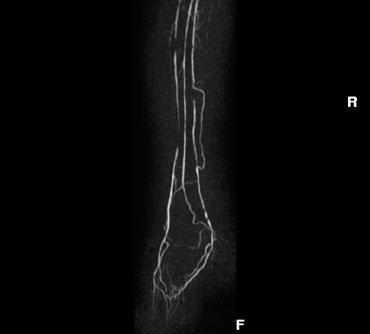

Ảnh MIP mặt phẳng đứng dọc của chuỗi TOF từ động mạch chủ đến mức bàn chân. Sự thay đổi về chiều rộng và góc nghiêng sẽ giúp bao phủ tốt hơn ở các vùng khác nhau.

Lập kế hoạch chuỗi chụp

Chuỗi CE-MRA có thể được lập kế hoạch dựa trên chuỗi TOF sơ bộ, giúp xác định vị trí các mạch máu cần khảo sát.